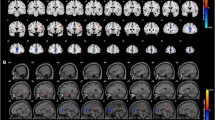

The fusiform and STG regions displayed preference toward both types of unmasked negative stimuli, with greater extracted univariate activity compared to the neutral stimulus conditions. The remaining ROIs did not demonstrate affect specificity for unmasked affective stimuli, and no ROIs demonstrated affect specificity toward masked stimuli. Fig. 2 shows the group-level results of the whole-brain conjunction analysis, presenting significant differences in univariate activities when comparing the three pairs of affective conditions (fear–fear mask, sadness–sadness mask, and neutral–neutral mask).

Study 1 fMRI—GLM results

We performed GLM analysis to examine variations in overall activity due to the affective conditions. Comparing the univariate activity for each affective condition and its corresponding masked condition, the AC, PC, IFG, STG, fusiform, and pulvinar exhibited greater activity, but the parietal region exhibited less activity. Along with the a priori ROIs (the pons and amygdala), these seven additional ROIs were used to inform subsequent analyses (see Materials and Methods section).